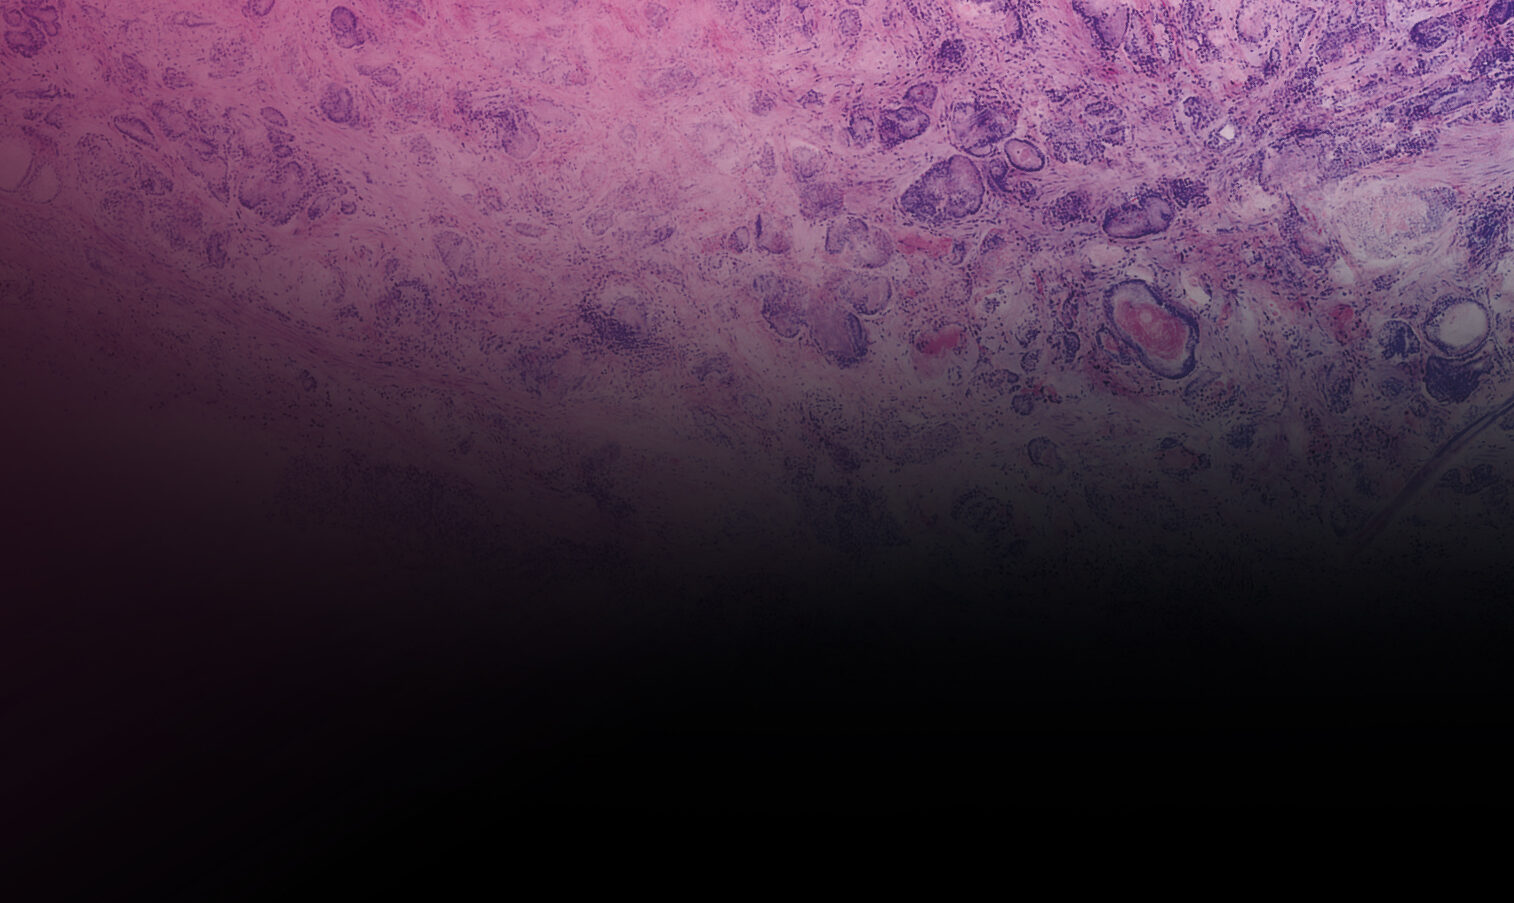

H&E-like images during surgery. Within minutes. Immediate results possible.

VivaScope technology is based on confocal microscopy (CLSM) and acquires images of superb optical resolution and contrast. Two lasers of different wavelengths create two distinct images, a fluorescence image and a reflectance image. Both signals are scanned simultaneously and are used to create pseudo-colored images. The device’s software uses an algorithm to translate the acquired image information into colors that resemble H&E. It’s not just digital pathology. Because you receive H&E like images during ongoing surgery, we call it “instant digital pathology”.

Basal cell carcinoma; imaged with the VivaScope 2500 (left) and after H&E staining (right)

The VivaScope 2500 enables intraoperative assessment of tumor margins as well as immediate examination of biopsies. Surgical workflows and patient management can thus be significantly improved. The acquired images show subcellular details of the examined tissue.